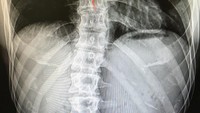

Padahal ia memiliki tulang punggung yang bengkok, atau dikenal sebagai scoliosis. Namun kondisi ini tak menyurutkan hobinya untuk olahraga. (Foto: instagram/kjk76)